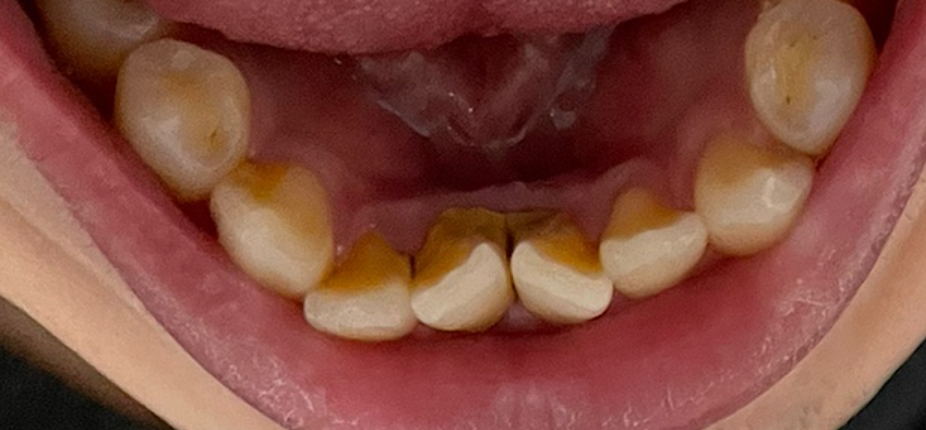

저는 치석이 주로 앞니 안쪽 편에 많이 있었는데요. 제 치석 사진입니다. (혐 주의)

병원에서 편안하게 스케일링을 해 주셔서 치석을 제거할 수 있었습니다.

아쉽게도 치석 떨어지고 나서 사진을 안 찍었었네요. 무슨 금속 덩어린 줄 알았었습니다 ^^;